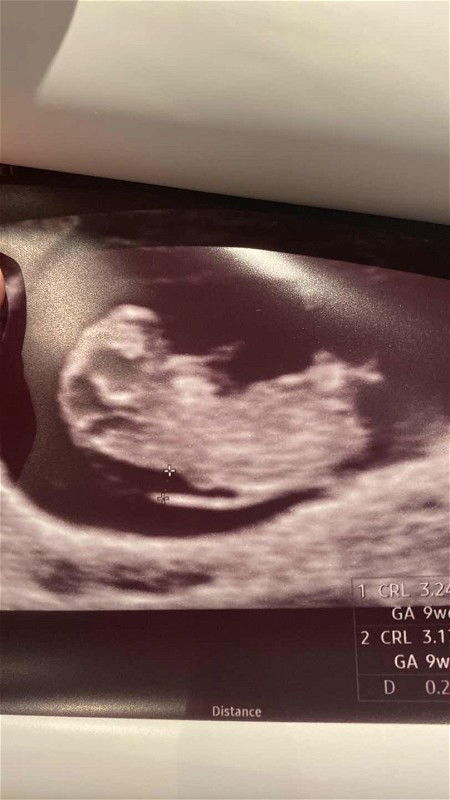

9wk6d ultrasound shows relatively high NT

Went for my 2nd routine check & gynae spotted this “gap” at the back that measures 2.8mm. My husband & I decided to make an appointment for both Oscar & NIPT as soon as we are able to. Still, I just can’t help but worry over it. Anyone who can share past experiences to ease my concern would be highly appreciated 🙏🏻 Update 23/7/23: FTS & NIPT both came out low risk 🥹 #firsttimemom #firstbaby